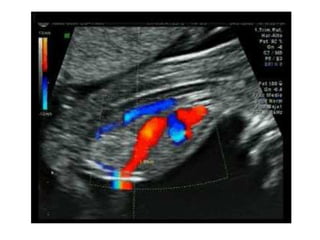

DOPPLER DE ARTERIAS UTERINAS

RIESGO DE

PREECLAMPSIA

DOPPLER DE ARTERIASUTERINAS RIESGO DE PREECLAMPSIA